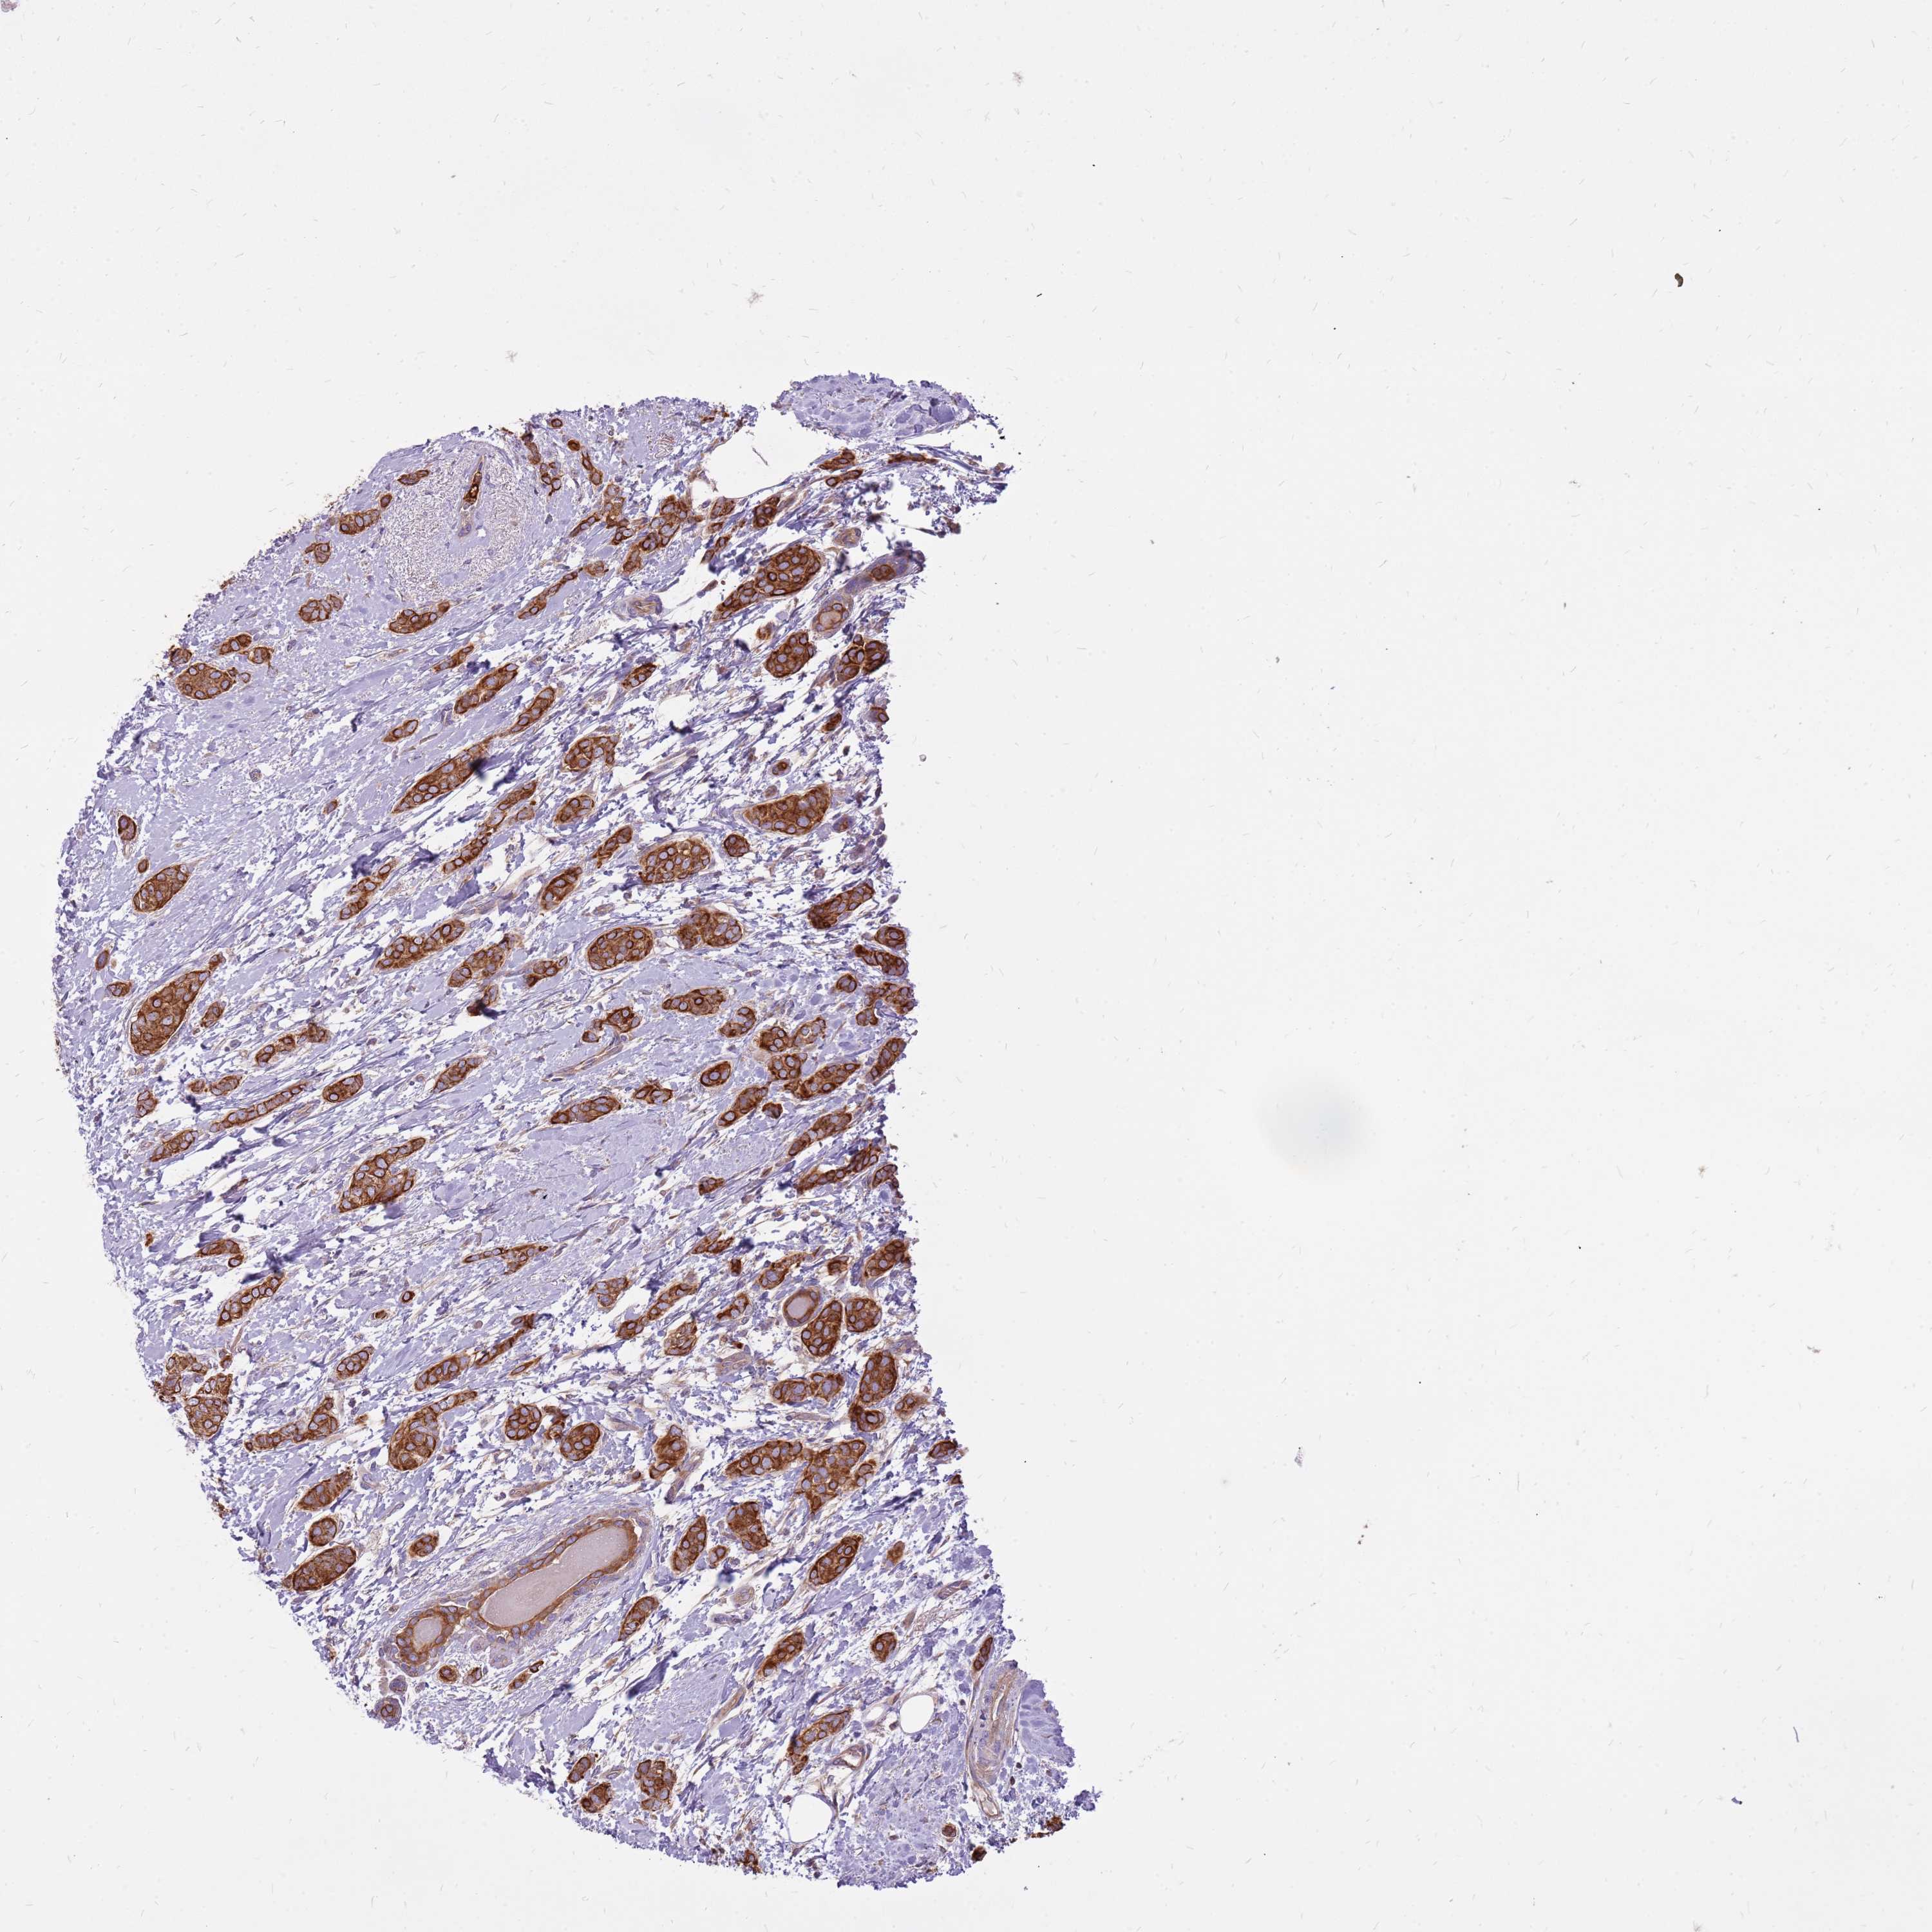

CANCER BREAST CANCER Show tissue menu

BRCA TCGA BRCA VALIDATION PROTEIN EXPRESSION